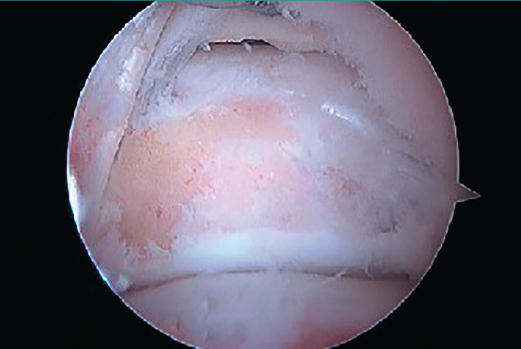

En ocasiones, está desprendido y se puede retirar fácilmente con una pinza grasper. Pero, si está fijado por fibrosis, es posible separarlo mediante el empleo de un desperiostizador o el sinoviotomo. Pero, cuando la fusión está calcificada, será preciso emplear un osteotomo de 5 mm introducido por el portal artroscópico. El fragmento escindido se extrae mediante una pinza grasper. También se puede utilizar un terminal de fresado para hacer la resección o para finalizarla regularizando los bordes del hueso. El límite del cartílago de la articulación subastragalina constituye el mejor punto de referencia para asegurarnos una resección adecuada (Figura 9).

Figura 9. Aspecto final después de la resección ósea. Se aprecia perfectamente el límite del cartílago de la articulación subastragalina.